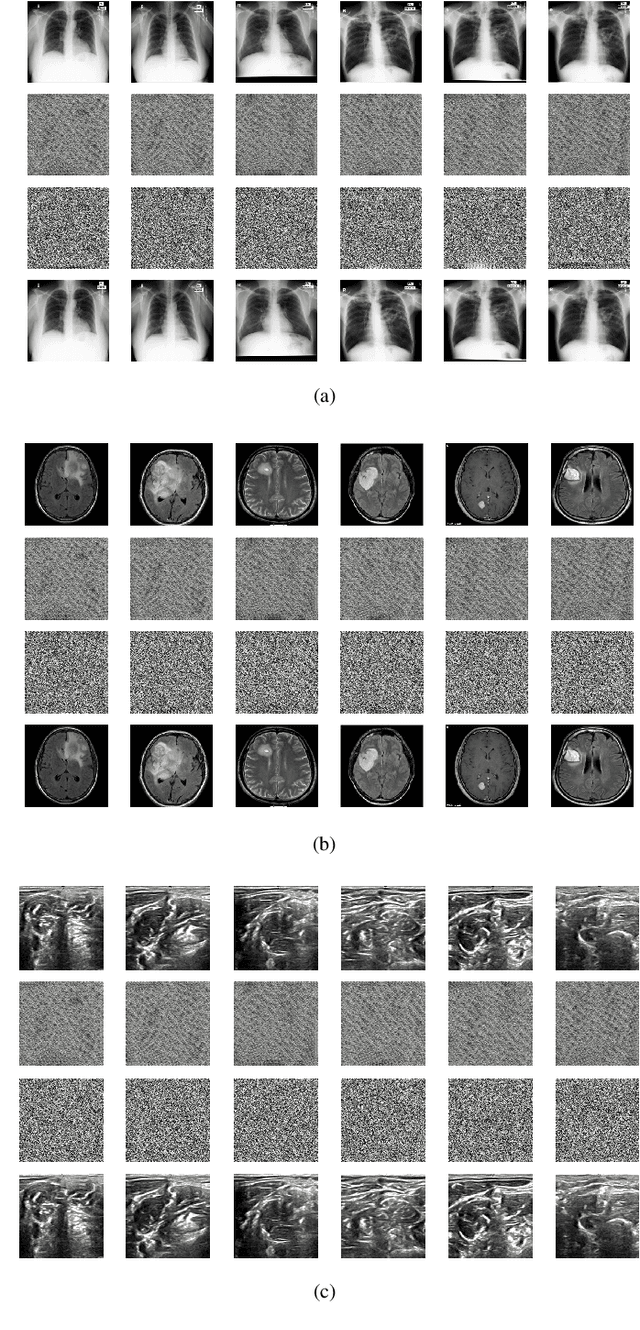

Abstract:The need for medical image encryption is increasingly pronounced, for example to safeguard the privacy of the patients' medical imaging data. In this paper, a novel deep learning-based key generation network (DeepKeyGen) is proposed as a stream cipher generator to generate the private key, which can then be used for encrypting and decrypting of medical images. In DeepKeyGen, the generative adversarial network (GAN) is adopted as the learning network to generate the private key. Furthermore, the transformation domain (that represents the "style" of the private key to be generated) is designed to guide the learning network to realize the private key generation process. The goal of DeepKeyGen is to learn the mapping relationship of how to transfer the initial image to the private key. We evaluate DeepKeyGen using three datasets, namely: the Montgomery County chest X-ray dataset, the Ultrasonic Brachial Plexus dataset, and the BraTS18 dataset. The evaluation findings and security analysis show that the proposed key generation network can achieve a high-level security in generating the private key.

Abstract:Internet of Medical Things (IoMT) can connect many medical imaging equipments to the medical information network to facilitate the process of diagnosing and treating for doctors. As medical image contains sensitive information, it is of importance yet very challenging to safeguard the privacy or security of the patient. In this work, a deep learning based encryption and decryption network (DeepEDN) is proposed to fulfill the process of encrypting and decrypting the medical image. Specifically, in DeepEDN, the Cycle-Generative Adversarial Network (Cycle-GAN) is employed as the main learning network to transfer the medical image from its original domain into the target domain. Target domain is regarded as a "Hidden Factors" to guide the learning model for realizing the encryption. The encrypted image is restored to the original (plaintext) image through a reconstruction network to achieve an image decryption. In order to facilitate the data mining directly from the privacy-protected environment, a region of interest(ROI)-mining-network is proposed to extract the interested object from the encrypted image. The proposed DeepEDN is evaluated on the chest X-ray dataset. Extensive experimental results and security analysis show that the proposed method can achieve a high level of security with a good performance in efficiency.